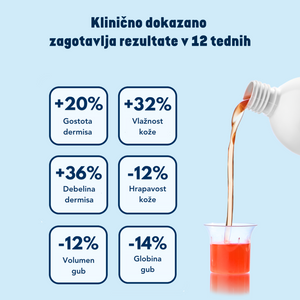

Do zdaj smo učinkovitost našega izdelka lahko upravičevali na podlagi vaših mnenj, od zdaj naprej pa lahko potrdimo, da so učinki Kolagen shot-a tudi klinično potrjeni.

Neodvisni inštitut je izvedel randomizirano, dvojno slepo, s placebom kontrolirano klinično študijo. V klinični študiji je sodelovalo 107 žensk, starih od 40 do 65 let.

Po 12. tednih uživanja formulacije, ki je vsebovala 5.000 mg kolagenskih peptidov, 1.500 MSM-ja in vitamina C, so rezultati pokazali:

- 20 % izboljšanje gostote dermisa

- 3,6 % izboljšanje debeline dermisa

- 32 % izboljšanje hidratacije kože

- 12 % izboljšanje teksture kože

- 14 % manjšo globino gub in za 12 % zmanjšan obseg gub

Več o klinični študiji, si lahko preberete tukaj.

Učinkovitost Kolagen Shota je bila dokazana z neodvisno klinično študijo, ki je pokazala, da redna uporaba prinaša vidne rezultate na koži.